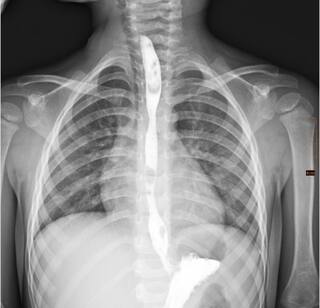

Ускладнення: згодом у пацієнта розвинувся критичний стеноз — просвіт стравоходу настільки звузився, що прийом їжі через рот став неможливим.

Унікальні операції: мультидисциплінарна команда вирішила відмовитися від великої травматичної операції на користь серії малоінвазивних втручань — балонних дилатацій. Під час цих процедур звужену ділянку поступово розширювали спеціальним балоном без жодних розрізів.